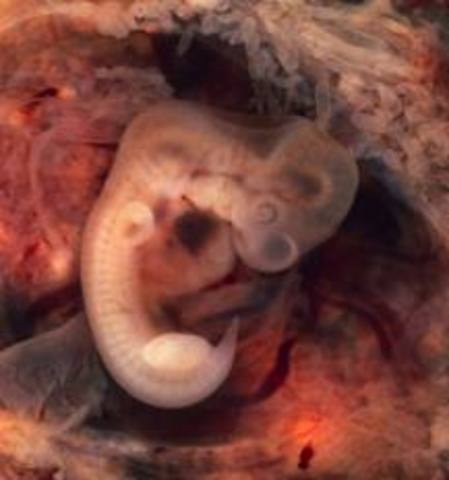

• Brain Begins to Form, Embryonic Phase Starts

Brain Begins to Form, Embryonic Phase Starts

• Heart Is Functioning, The Neural Tube Begins to Close

Heart Is Functioning, The Neural Tube Begins to Close

The neural tube will eventually form the spinal cord. At this point basic facial features are also beginning to develop. The digestive tract has also begun development, as well as the spine.